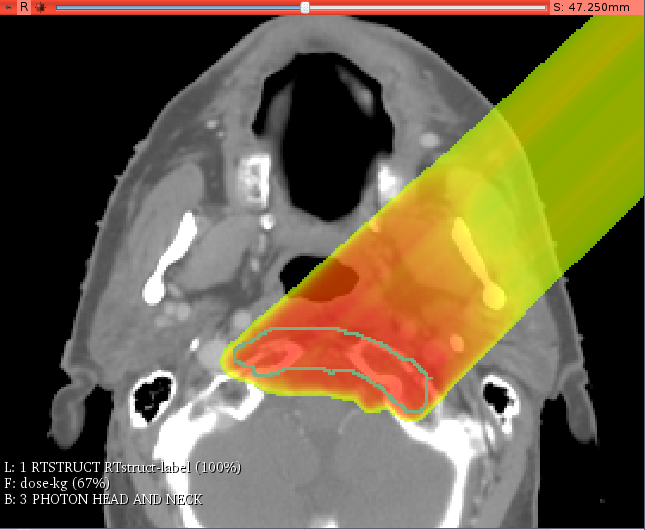

Project Week 25/EBP

- Gregory Sharp (Massachusetts General Hospital, Harvard Medical School, USA)

- Csaba Pinter (Queen's University, Canada)